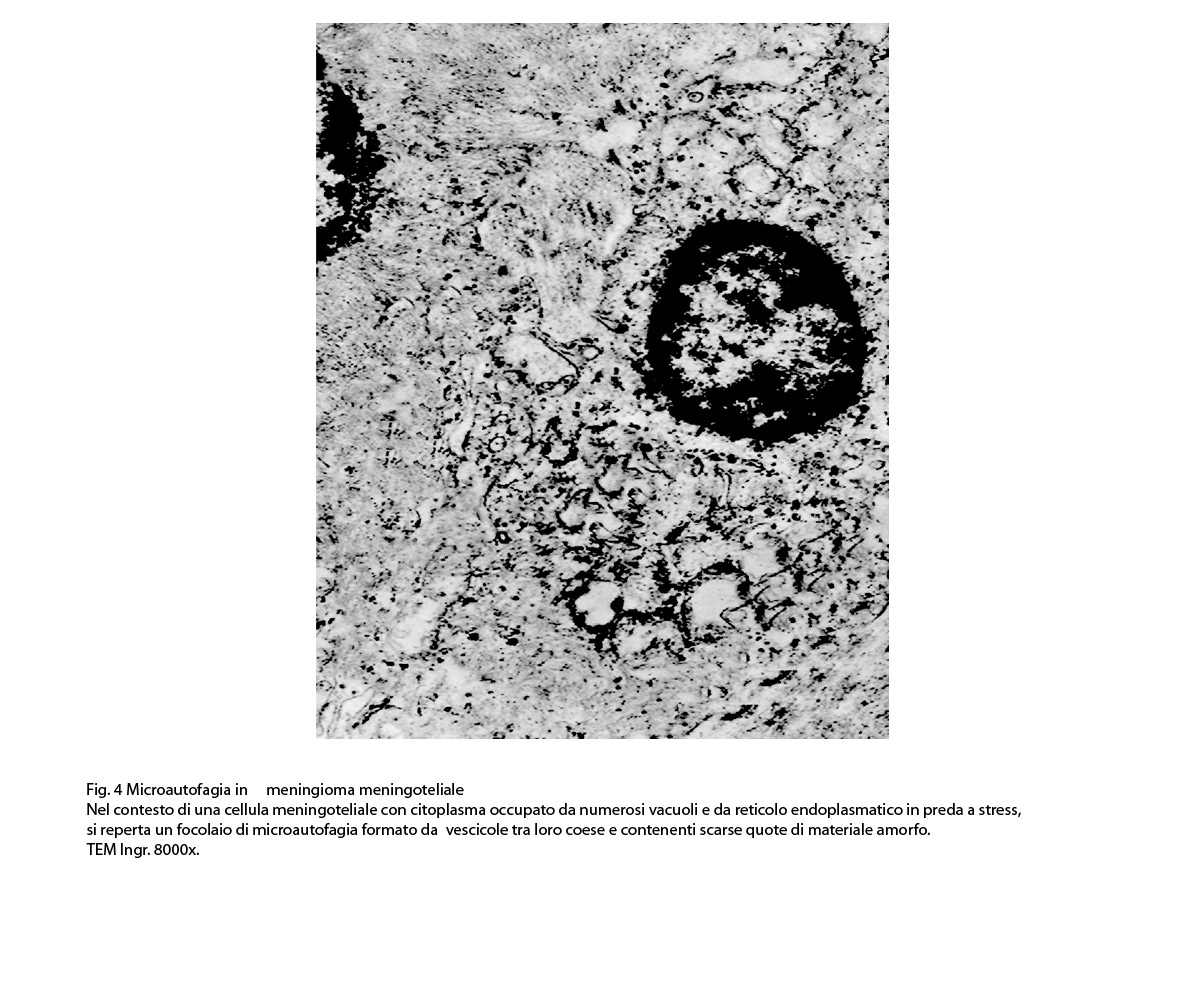

1) MICROAUTOFAGIA

Nel citosol si repertano vescicole di piccole dimensioni delimitate da una membrana di contorno a mono strato. Il loro lume è occupato da materiale amorfo e da corti filamenti distribuiti in modo disordinato.

Queste vescicole sono distribuite in modo irregolare, anzi casuale e si ritrovano ad essere isolate o riunite in piccoli aggregati formando un’immagine definita corpi multivescicolari.

Frequentemente questi focolai si ritrovano commisti ad altri aventi i caratteri della macroautofagia e sono in parte da questi mascherati. A parte questi particolari reperti,il citosol è occupato da numerosi mitocondri di piccole dimensioni e di forma rotondeggiante e di aspetto compatto,da ergastoplasma rugoso e da quote ben rappresentate di reticolo endoplasmico e di strutture lisosomiali.